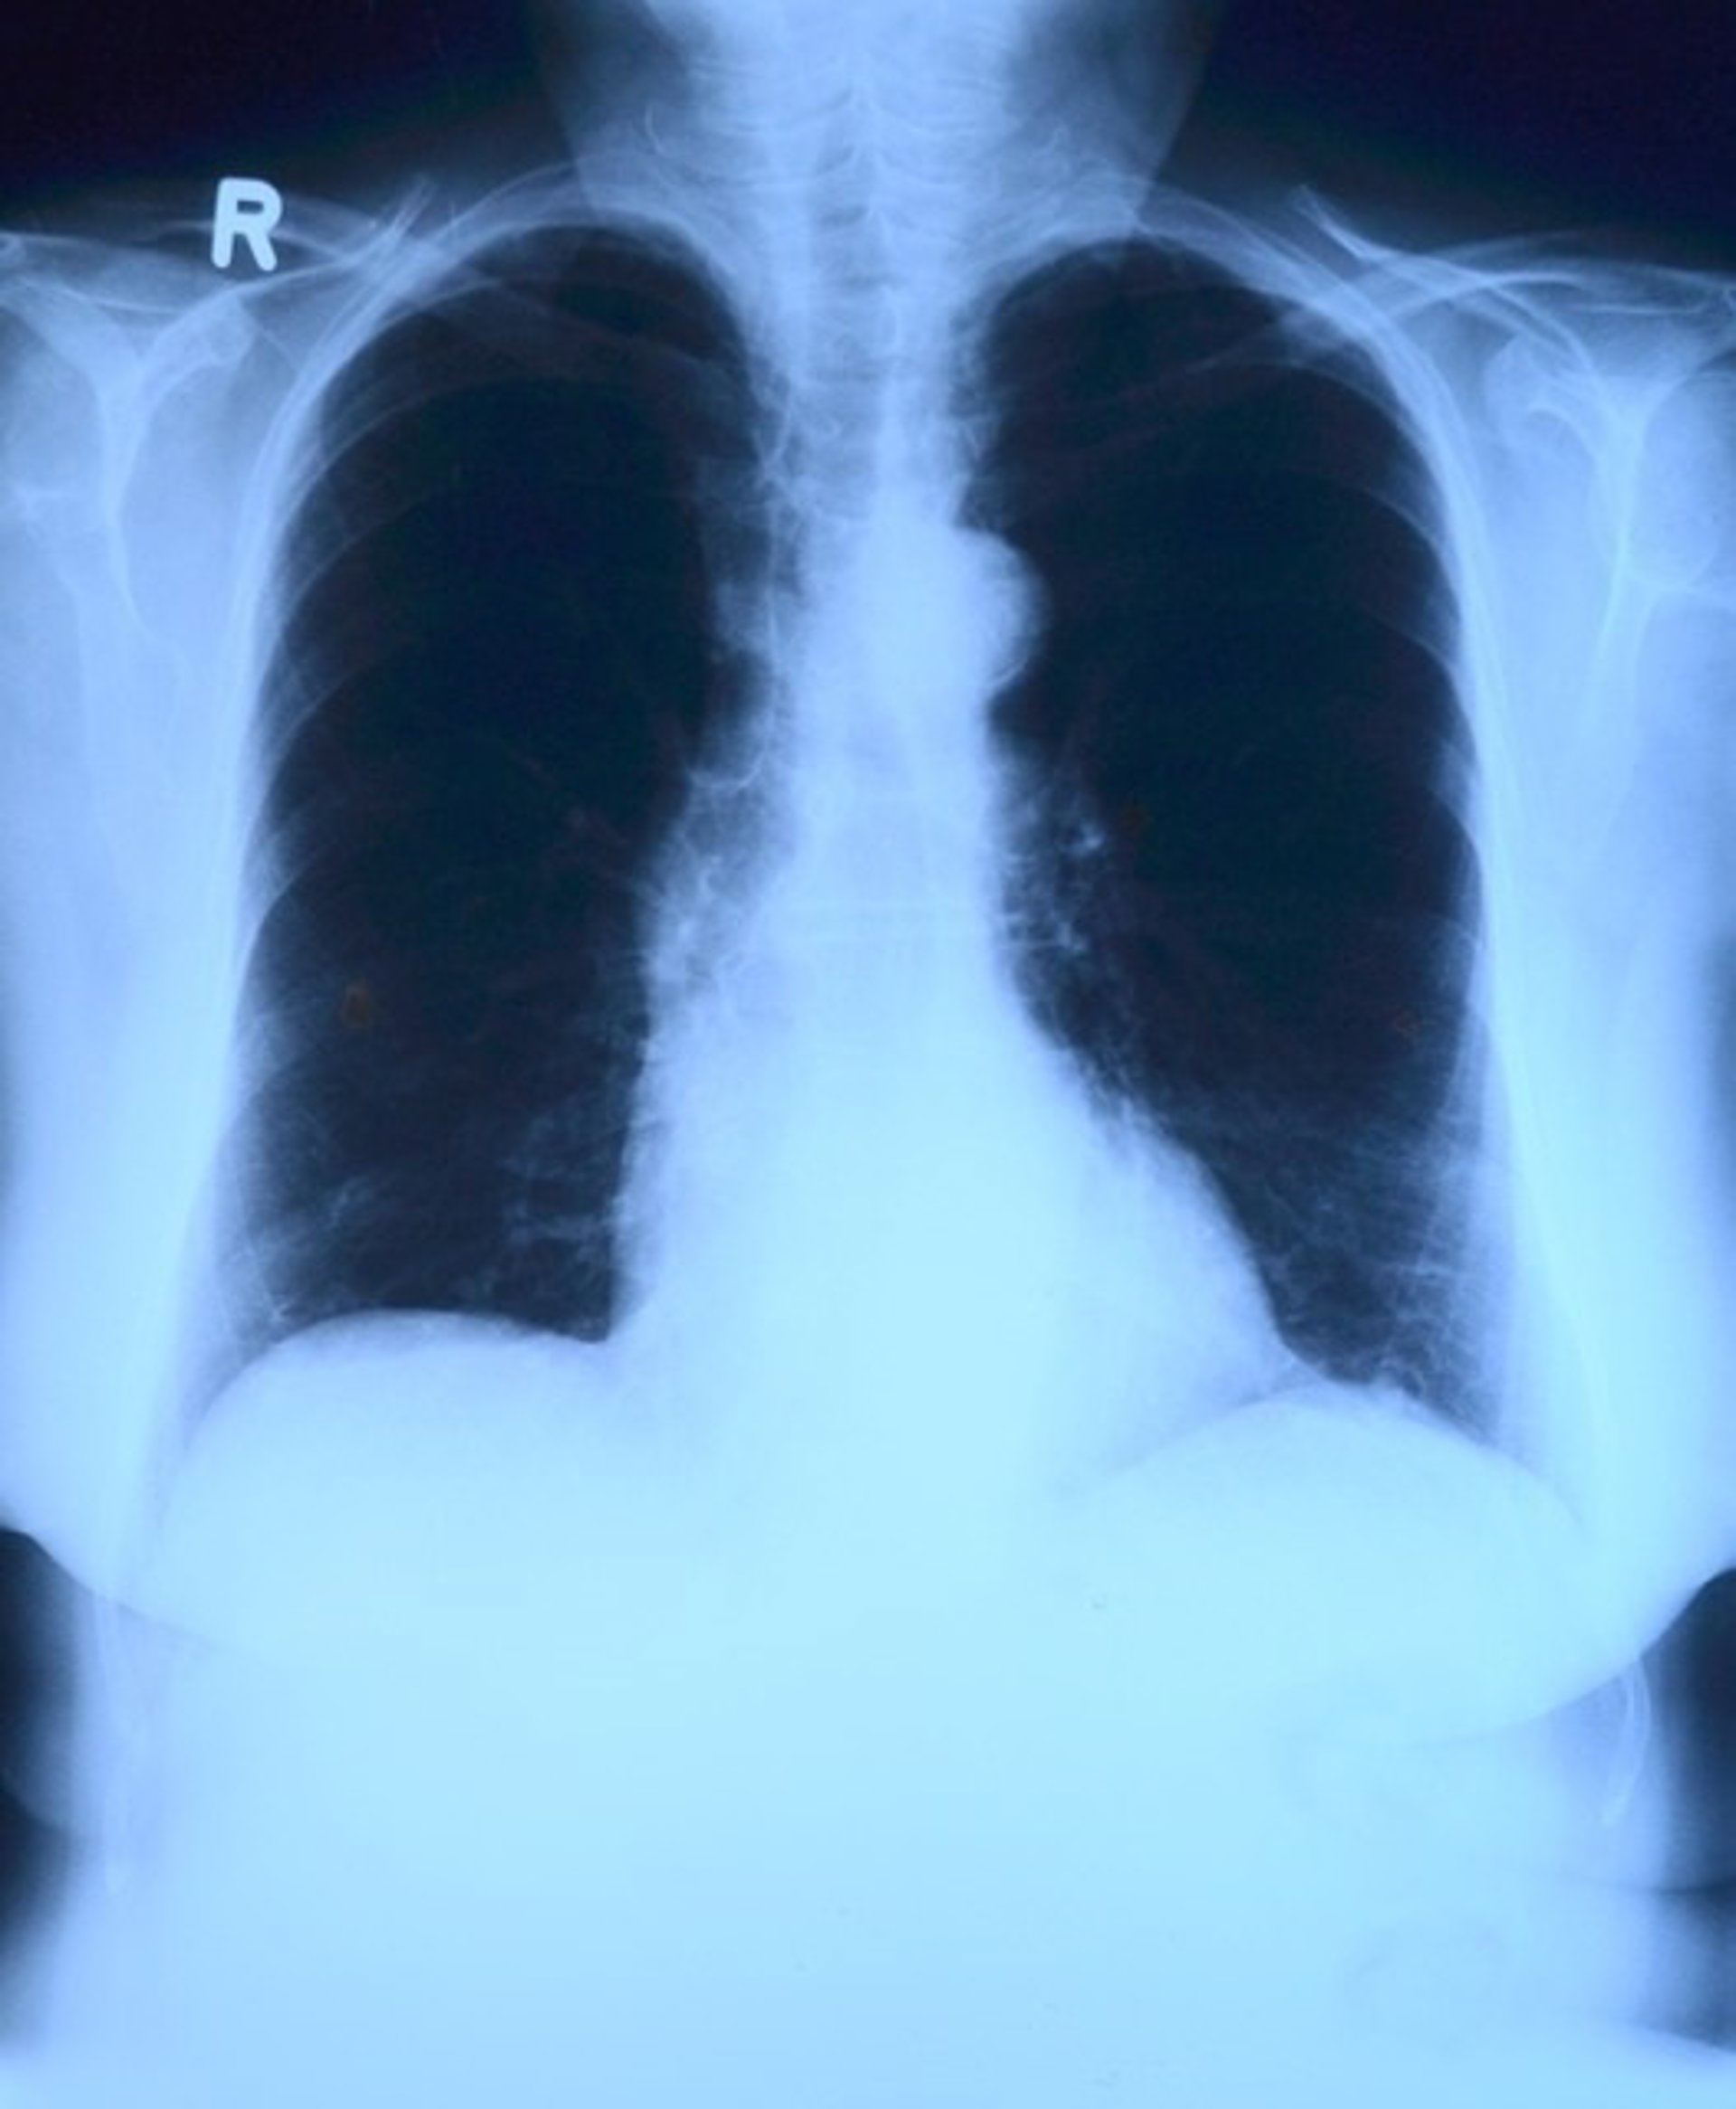

Pulmones, radiografía

PIXABAY